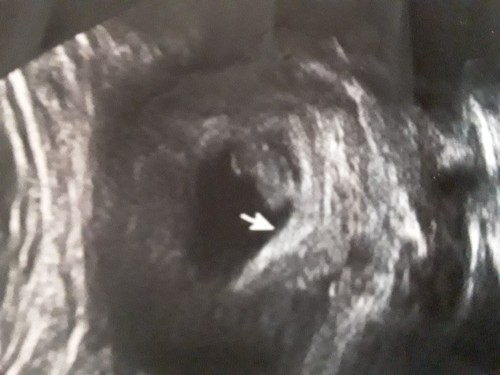

Görür görmez içinize ne doğdu

Canım Bu haftalarda nub her iki tarafa da benzer yani Nasıl yorum yapayım ki başka usg var mı yine 9 haftaya ait veya 8. Hafta

İçimden kuz geçti nedense ama şimdi fasulye kadar daha çok erken gibı cinsiyet için

Bebek var orda.